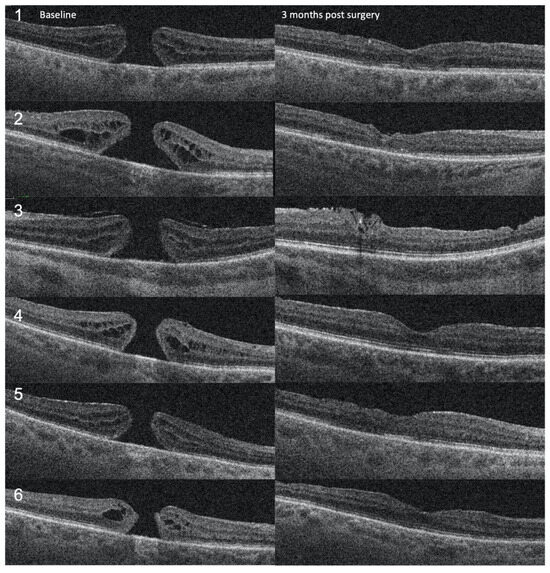

Figure 1

Background: The purpose of this study was to evaluate the anatomical and visual outcomes of patients with stage IV full-thickness macular holes (FTMHs) treated by the cabbage leaf inverted internal limiting membrane (ILM) flap technique. Methods: We conducted a retrospective study, enrolling patients [...] Read more.

Background: The purpose of this study was to evaluate the anatomical and visual outcomes of patients with stage IV full-thickness macular holes (FTMHs) treated by the cabbage leaf inverted internal limiting membrane (ILM) flap technique. Methods: We conducted a retrospective study, enrolling patients with stage IV FTMH operated by a single surgeon. Six patients with FTMH and no other known ocular comorbidities were included in the study. Results: Four patients (66.6%) were female, two were male. The median age was 71. The average duration of symptoms before surgery was 10.5 months (6–24 months). The mean preoperative minimum hole diameter was 480 μm (337–602), and the mean basal hole size was 1208 μm (703–1748). The mean preoperative BCVA was 0.63 LogMAR. Postoperatively, the BCVA improved in 5 (83.3%) patients and remained the same in 1 (16.7%). The mean postoperative BCVA was 0.42 LogMAR (0.0–0.70). The FTMH has closed in all cases (100%). At the follow-up examination three months after the surgery, we observed complete closure of the FTMH with the restoration of retinal layers. Conclusions: This approach resulted in a complete closure of FTMH with significant visual acuity improvement. The technique could represent the surgical procedure of choice in the management of stage IV FTMH. Full article